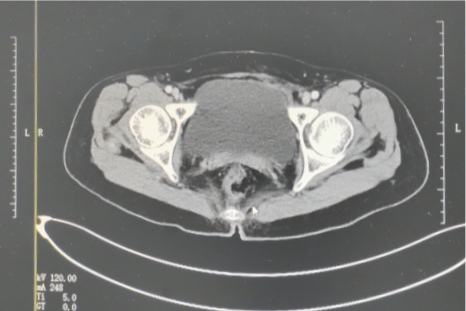

2024年6月,阿宝复查影像图像

阿宝的宫颈肿瘤呈菜花样,伴有阴道出血。影像结果提示肿瘤位于宫颈后壁,考虑有宫颈癌的可能。最终,活检结果提示为中-低分化鳞状细胞癌。秉着对复大、对李红梅副主任的信任,2023年7月,阿宝接受了腹式广泛性全子宫切除术和盆腔淋巴结清扫术。术后病理为(子宫颈)低分化鳞状细胞癌,IB2期。根据术后病理结果,阿宝又补充了2个疗程的辅助化疗。经过针对性治疗,阿宝多次复查结果都显示其恢复良好,未见肿瘤病变。